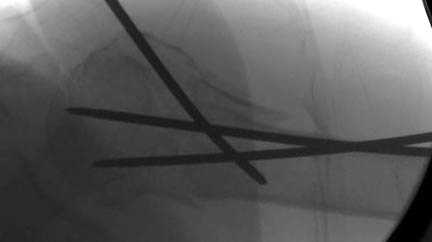

Наш недавний случай перкутанной фиксации "методом

Сиэтла" спицами 2.8 мм с резьбой на конце.

Имя     : 5 Proximal humerus CRM.jpg

Url     : http://weborto.net:8080/pipermail/ortho/attachments/20071128/ffd31465/attachment-0008.jpg